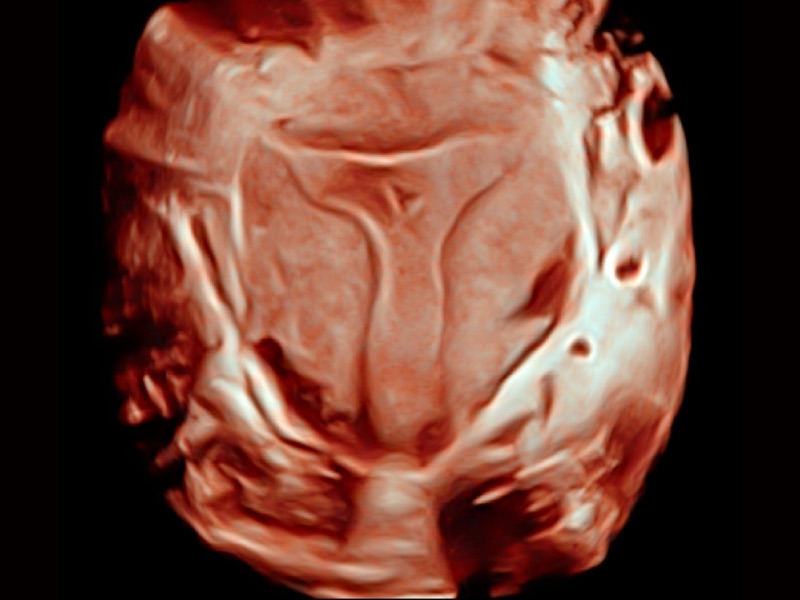

• 光影成像

临床图